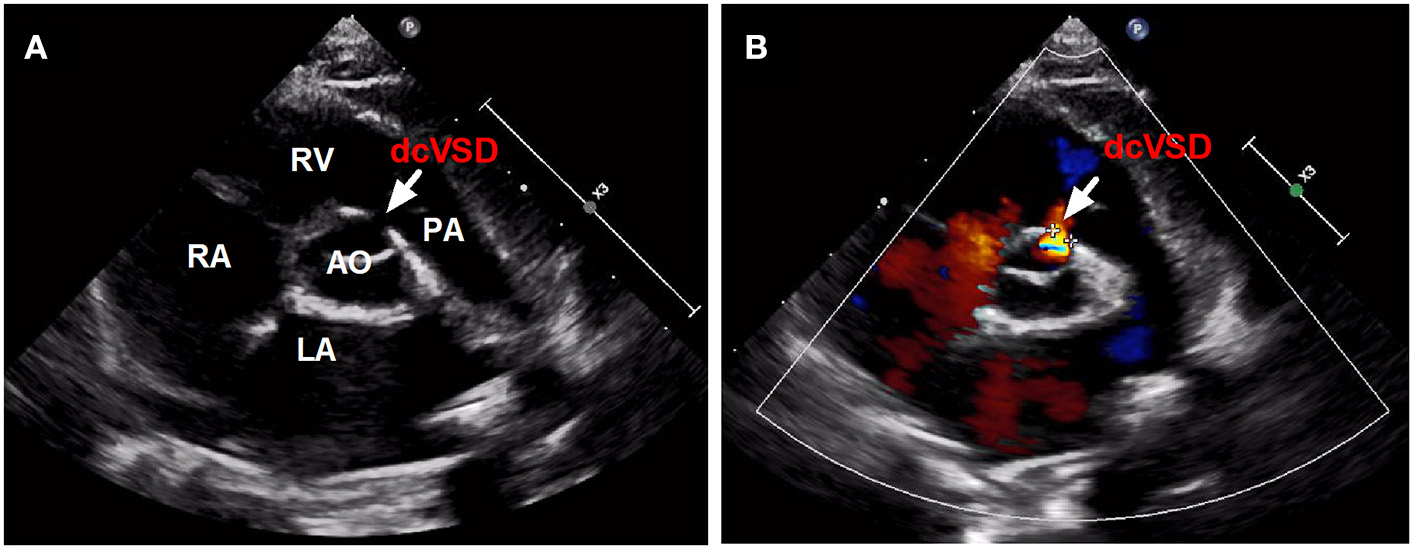

Between January 2016 and April 2021, all children with dcVSD who underwent transfemoral closure using the ADO-II at our center were screened. The diagnosis of dcVSD was confirmed by transthoracic echocardiography (TTE), based on its position on an analog clock face in the short-axis parasternal view with the observation of dcVSD between the 1 and 2 o'clock directions (Figure 1) (15, 16). Aortic valve prolapse (AVP) was graded on a three-point scale: mild (buckling of the aortic cusp down the left ventricular [LV] outflow tract with minimal herniation into the VSD), moderate (prolapse of the cusp with obvious herniation and its sinus into the VSD), and severe (prolapse of the cusp and its sinus through the defect into the right ventricular [RV] outflow tract) (17, 18). AR was quantified using the ratio of jet width and LV outflow tract (LVOT) diameter. AR was classified as trivial (jet width/LVOT diameter < 10%), mild (jet width/LVOT diameter = 10–24%), moderate (jet width/LVOT diameter = 25–49%), and severe (jet width/LVOT diameter > 50%) (19).

Figure 1

The confirmed diagnosis of dcVSD by TTE. Parasternal short-axis view (A,B) on TTE shows the dcVSD located at the 1-2 o'clock position (arrows). AO, aortic; LA, left atrium; RV, right ventricle; RA, right atrium; PA, pulmonary artery; dcVSD, doubly committed subarterial ventricular septal defect; TTE, transthoracic echocardiography.